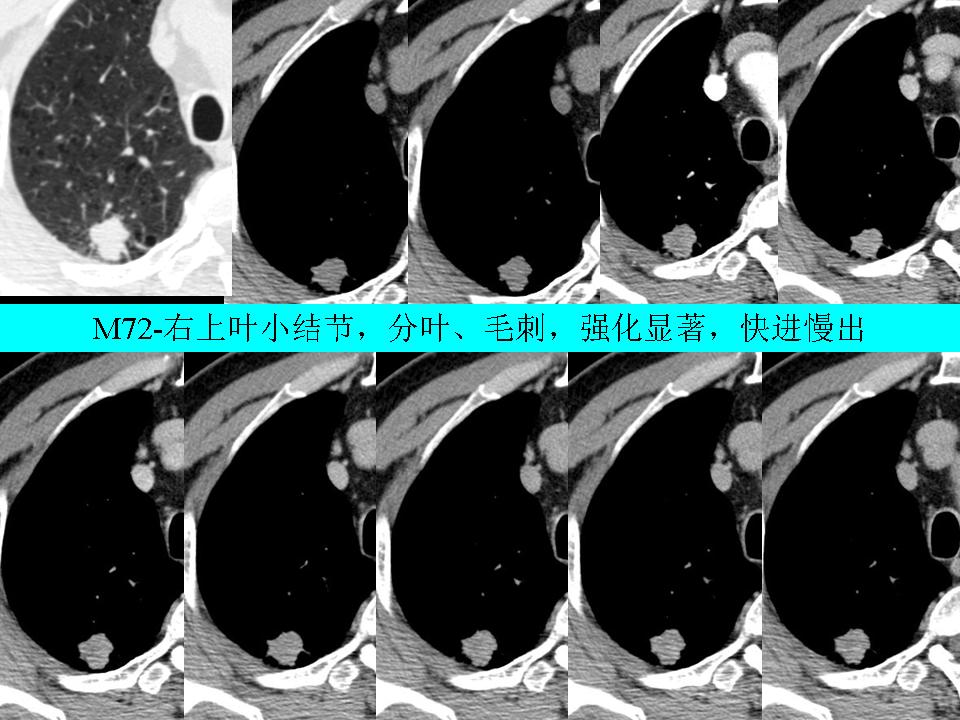

周围型肺癌的影像诊断